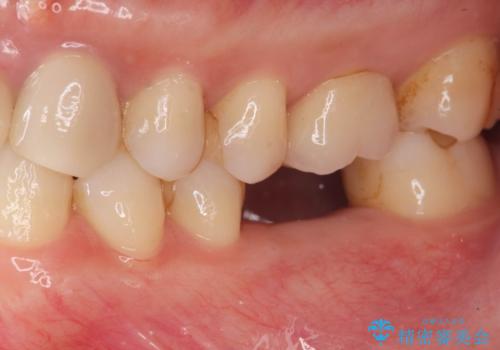

欠損部のインプラント補綴

- 失った奥歯にインプラント治療を受けたい、と希望され来院されました。

前後の歯を削らずに機能回復できるインプラントを用いて審美生、咬合機能の回復を計画します。